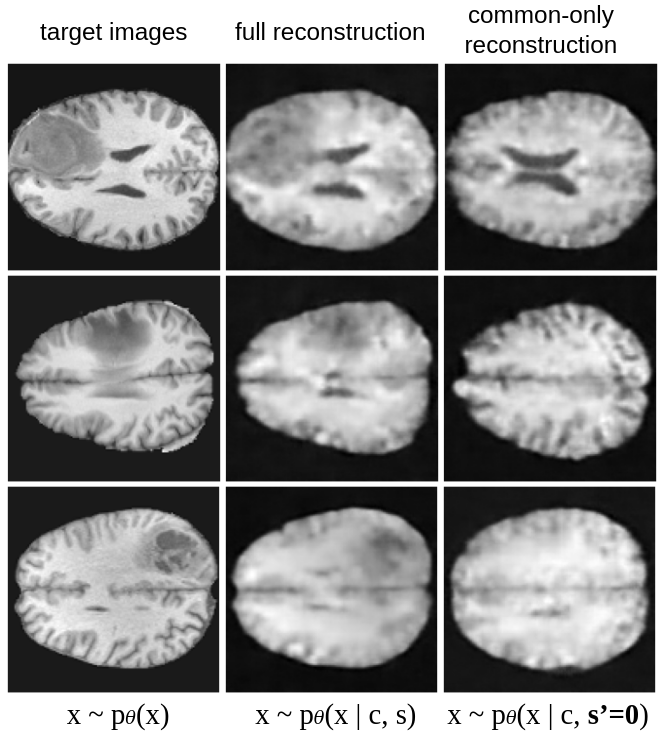

Qualitatively, the model can be evaluated by looking at the full image reconstruction (common+salient factors) and by fixing the salient factors to for target images. Comparing full reconstructions with common-only reconstructions allows the user to interpret the patterns encoded in the salient factors (see Fig.1 and Fig.5).

Given a background population of Healthy Controls (HC) and a target population suffering from a Mental Disorder (MD), the objective is to capture the pathological factors of variability in the salient space, such as psychiatric and cognitive clinical scores, while isolating the patterns related to demographic variables, such as age and sex, or acquisition sites to the common space. For each experiment, we gather T1w anatomical VBM (Ashburner & Friston, 2000) pre-processed images resized to 128x128x128 of HC and MD subjects. We divide them into 5 TRAIN, VAL splits (0.75, 0.25) and evaluate in a cross-validation scheme the performance of SepVAE and the other SOTA CA-VAE methods. Please note that this is a challenging problem, especially due to the high dimensionality of the input and the scarcity of the data. Notably, the measures of psychiatric and cognitive clinical scores are only available for some patients, making it scarce and precious information.

We merged images of schizophrenic patients (TG) and healthy controls (BG) from the datasets SCHIZCONNECT-VIP (Wang et al., 2016) and BSNIP (Tamminga et al., 2014). Results in Tab. 4 show that the salient factors estimated using our method better predict schizophrenia-specific variables of interest: SAPS (Scale of Positive Symptoms), SANS (Scale of Negative Symptoms), and diagnosis. On the other hand, salient features are shown to be poorly predictive of demographic variables: age, sex, and acquisition site. It paves the way toward a better understanding of schizophrenia disorder by capturing neuro-anatomical patterns that are predictive of the psychiatric scales while not being biased by confound variables.

Second, we combine patients with autism from ABIDE1 and ABIDE2 (Heinsfeld et al., 2017) (TG) with healthy controls (BG). In Tab. 4, SepVAE’s salient latents better predict the diagnosis and the clinical variables, such as ADOS (Autism Diagnosis Observation Schedule) and ADI Social (Autism Diagnosis Interview Social) which quantifies the social interaction abilities. On the other hand, salient latents poorly infer irrelevant demographic variables (age, sex, and acquisition site), which is a desirable feature for the development of unbiased diagnosis tools.